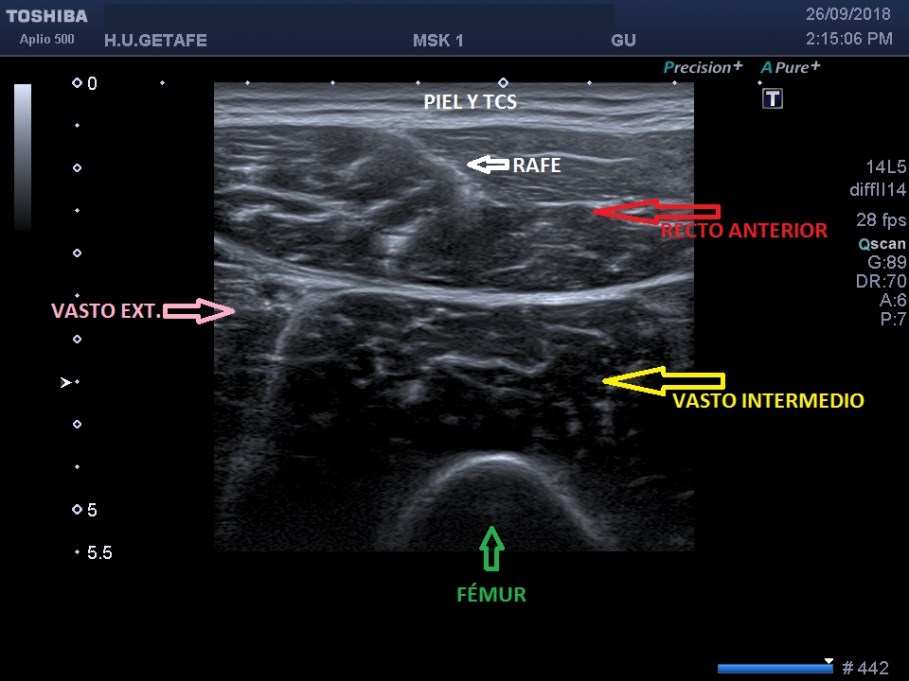

Un breve recuerdo anatómico de la zona tanto en eje largo como en eje corto (longitudinal o transverso), fig 3 y 2 respectivamente, . Fíjese la/el lectora en el posicionamiento del pictograma de referencia.

La exploración es la habitual, revisión sistemática de toda la ecoarquitectura musculoesquelética de la cara anterior del muslo, dirigido al Cuádriceps.

Me llama poderosamente la atención, lo recuerdo perfectamente, la normalidad del recto anterior, pero después de buscar un poco observo como el vasto intermedio si está «distinto», algo heterogéneo, voy a comparar con el lado contralateral y bingo¡ el vasto intermedio, que es de esa musculatura «que nunca tiene nada», modo «ironía on», te sorprende…y la ecografía muscular es como el océano, nunca puedes confiarte…

La zona que presenta mayor abombamiento y empastamiento (cara lateral del muslo izquierdo), se visualiza aumento del grosor del fascículo muscular correspondiente con el vasto intermedio, sin poder evidenciarse la presencia de lesiones definidas. El diagnóstico es un aumento difuso e inespecífico del Vasto Intermedio, sin masas ni roturas. A valorar con RMN.